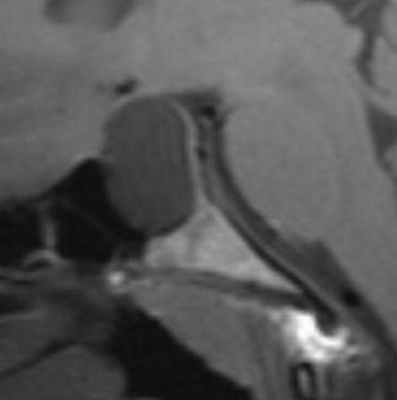

Киста кармана Ратке представляет собой редко встречающееся образование из остатков эмбриональной эктодермы (щель Ратке), расположенное между долями гипофиза. Выявляется в любом возрасте, но чаще в 50-60 лет. Клинические проявления связаны с масс-эффектом. При МРТ головного мозга выявляется небольшая (3-5мм) киста с четким контуром, без отека вокруг, однородная по структуре. Сигнал на МРТ головного мозга зависит от содержимого. При серозном содержимом сигнал типично жидкостный, при мукоидном киста светлая на Т1-взвешенных МРТ головного мозга. В 70-80% случаев внутри кисты выявляется неконирастирующийся узелок («пятно») – признак патогномоничный для кисты кармана Ратке. В редких случаях киста достигает больших размеров и даже выходит за пределы седла. Стенка кисты иногда усиливается при МРТ головного мозга с контрастированием. Дифференциальная диагностика при МРТ головного мозга должна проводиться с арахноидадьной и эпидермоидной кистами, тератомой, кистозной аденомой гипофиза и краниофарингиомой. Иногда при МРТ головного мозга киста кармана Ратке напоминает “пустое” турецкое седло. При маленьких размерах кисты ее на до дифференцировать на МРТ с микроаденомой гипофиза.

![Ratke cleft cyst]()

МРТ головного мозга. Т1-взвешенная сагиттальная МРТ. Киста кармана Ратке.